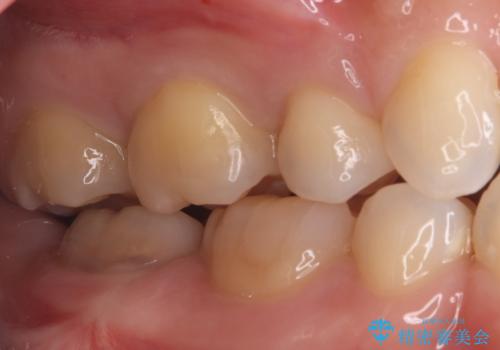

- 右上5番(小臼歯)の咬み合わせの面(咬合面)に小さな穴があることを主訴にご来院されました。視診およびレントゲン検査の結果、表面の穴は小さいものの、内部で虫歯が広がっていることが確認されました。患者様から「目立たないように治したい」というご希望があったため、健全な歯質を極力残しながら、審美性と耐久性に優れた**セラミックインレー(詰め物)**で修復する計画を立案しました。

後日、歯の色調に合わせてオーダーメイドで作製されたセラミックインレーを装着。セラミックは天然歯のような透明感があるため、修復した箇所がどこかわからないほど自然な仕上がりとなりました。